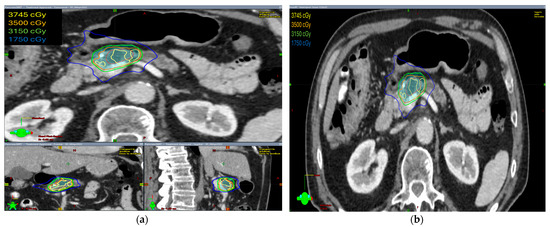

The radiation prescription dose was 35 Gy in five fractions in ten patients (58.8%). In five patients, the dose prescription was reduced to 30–33 Gy in five fractions and two patients received 40–50 Gy in five fractions. Median GTV volume was 28.60 cc (range 4.9–145.8 cc), median ITV was 29.15 cc (range 5.0–149.7 cc), and median PTV was 75.1 cc (range 19.9–255.3 cc). The isodose distribution for both abdominal compression and breath-hold technique is shown in Figure 1 and Figure 2, respectively.

The isodose distribution curves for target coverage and normal tissue dosing were evaluated. We found that the ITV was generated only in patients with abdominal compression to encompass the internal organ motion during treatment. Hence, PTV volumes were larger in these patients as compared with patients treated with breath-hold in which no ITV was drawn and smaller PTV volumes were irradiated.

Figure 2. The isodose distribution using the breath-hold technique (a) axial, coronal, and sagittal views (b) axial view.